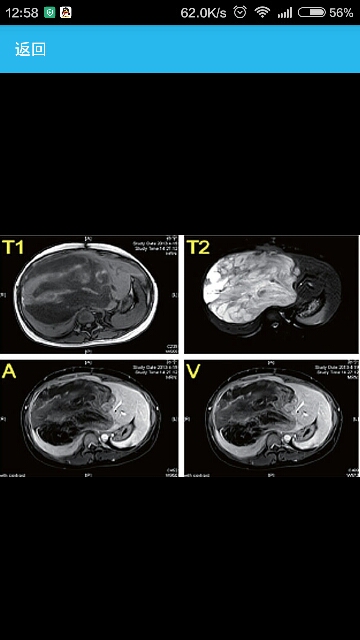

辅助检查B超及CT发现肝右叶巨大占位。

术中可见,腹腔内无腹水,未见转移结节,肝脏实质尚正常;于中央区肝7、8及部分4、5段表面可见一巨大囊实性肿物,直径约17cm,质地软,有包膜;胆囊8cm×4cm×3cm,胆囊壁无增厚,与周围组织无粘连,胆总管未见异常;肝十二指肠韧带未及肿大淋巴结,胃肠无特殊。 术后病理检查结果提示,肝切除标本为肝脏UESL,大小约12cm×9cm×13cm,并出血、坏死,部分肿瘤裸露,肝被膜未见肿瘤累及,周围肝组织轻度慢性肝炎;第二肝门切缘及中肝静脉旁均未见癌转移。免疫组化(IHC)染色检查,α-抗胰蛋白酶(a-AAT)(+),甲胎蛋白(AFP)(-),波形蛋白(VIM)(+),细胞角蛋白(CK)18(灶+),CK19(灶+),肝细胞(HEP)(-),CD31(血管+),神经组织蛋白(S-100)(-),人黑色素瘤相关抗原(HMB45)(-),突触素(Syn)(-),人平滑肌肌动蛋白(SMA)(-),结蛋白(Desmin)(-),CK(广)(-),CD68(+),核蛋白(Ki67)(50%+)。特殊染色结果,过碘酸雪夫染色(PAS)(+),抗淀粉酶消化的PAS(+)。